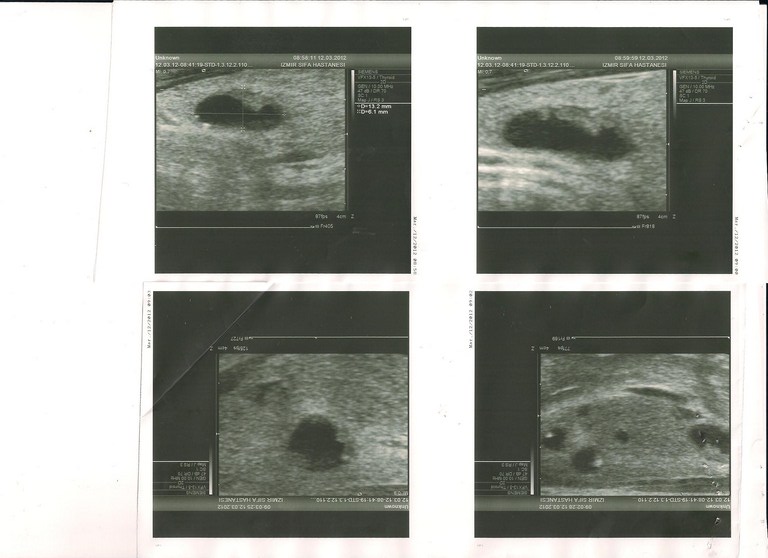

| | . .

03.2011 Tiroid Doppler US

14x15x48

12x12x40

2

7.5 , 10 , 5 . 1,5 2 .

4,5 . .

. . (RI: 0,53).

03.2011

. . . .

06.2011 Tiroid Doppler US

15x13x42

12x11x41

2,5

.

5,5 7 , 9 , .

5 .

. . , , . (RI: 0,54)

FT3 -

FT4 -

TSH -

03.2012 Tiroid US

17x15x46

16x17x47

2,7

- 136 , . - .

2,2 5,4 2,1 2,7 .

ANTI TPO - 84,11

, . - ( ). ? - , ? 28 , ..